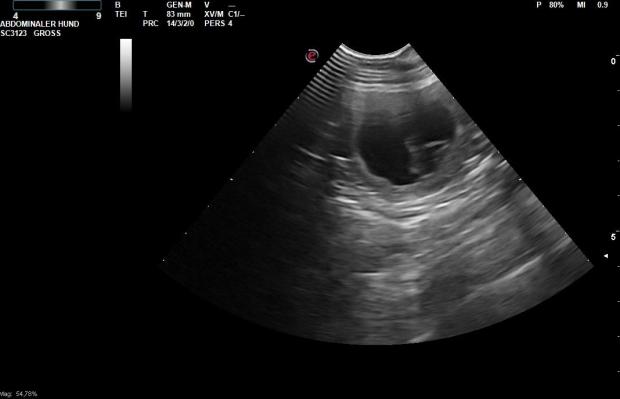

Am 27. Tag der Trächtigkeit waren wir beim Ultraschall. Laut Tierärztin ist Amira trächtig.